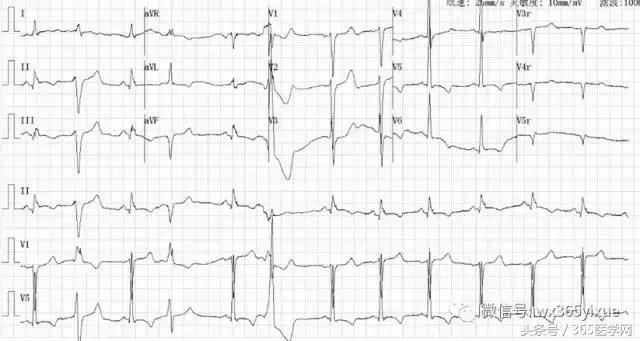

ECG